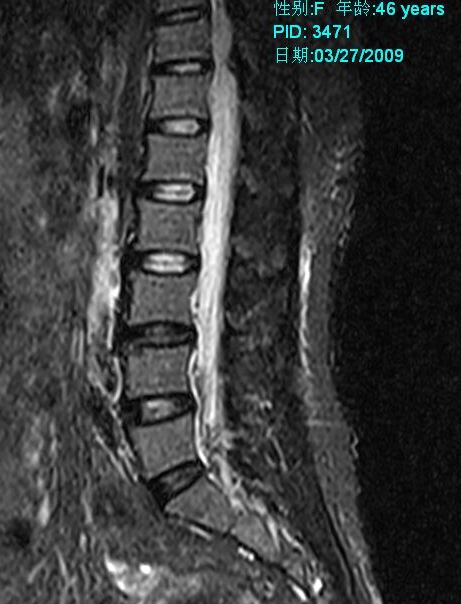

标题: MRI2099:此病人加做压脂像确诊为:终丝脂肪浸润。 [打印本页]

标题: MRI2099:此病人加做压脂像确诊为:终丝脂肪浸润。

此病人加做压脂像:腰1、2椎体平面椎管内条状高信号病灶信号明显降低。以下为压脂像图像: